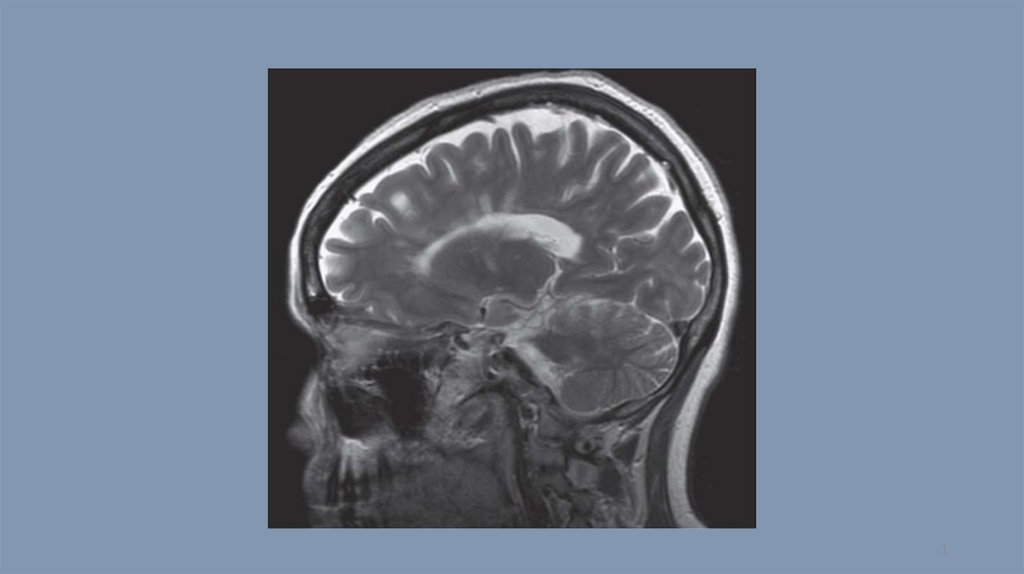

Компьютерная томография. Тест 14